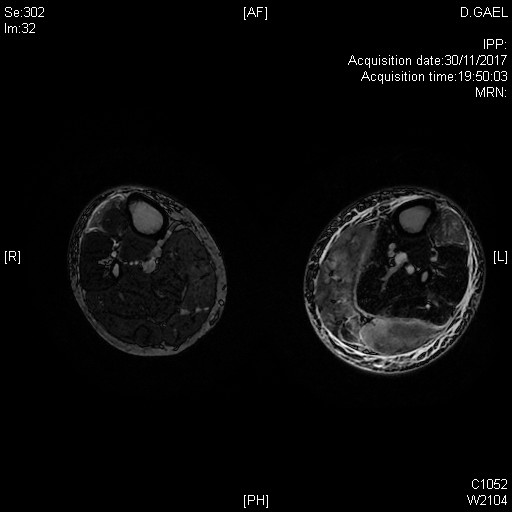

Hypersignaux T2 des muscles de la jambe dans le cadre d'un tableau clinique de dermatomyosite à auto-anticorps négatifs, révélée par une atteinte brutale oedémateuse

Tableau clinique de polymyosite avec atteinte clinique et IRM des deux jambes